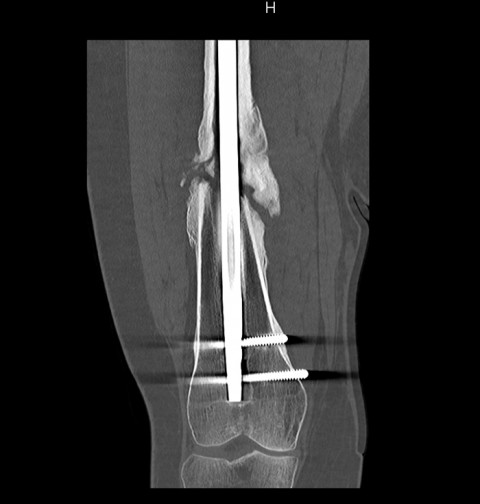

Bei einem schweren Verkehrsunfall zog sich eine 22-jährige junge Frau ein gravierendes Polytrauma zu. Durch die unverschuldete Kollision ihres Motorrades mit einem Personenwagen wurde ihr Oberschenkel auf der rechten Seite zertrümmert. Gleichzeitig kam es zu einem ausgeprägten Weichteildefekt an der Innenseite des Oberschenkels. Der Knochen wurde aufgrund der offen liegenden Knochenanteile mit einem äusseren Fixateur stabilisiert. Nach Deckung des ausgeprägten Weichteildefektes konnte ein Marknagel eingebracht werden. Leider kam es in der Folge nicht zu einer Ausheilung, sondern zu einer Auslockerung des Marknagels und einer Pseudoarthrose, welche wiederum mit einer Varusfehlstellung kombiniert war (Bild 1).